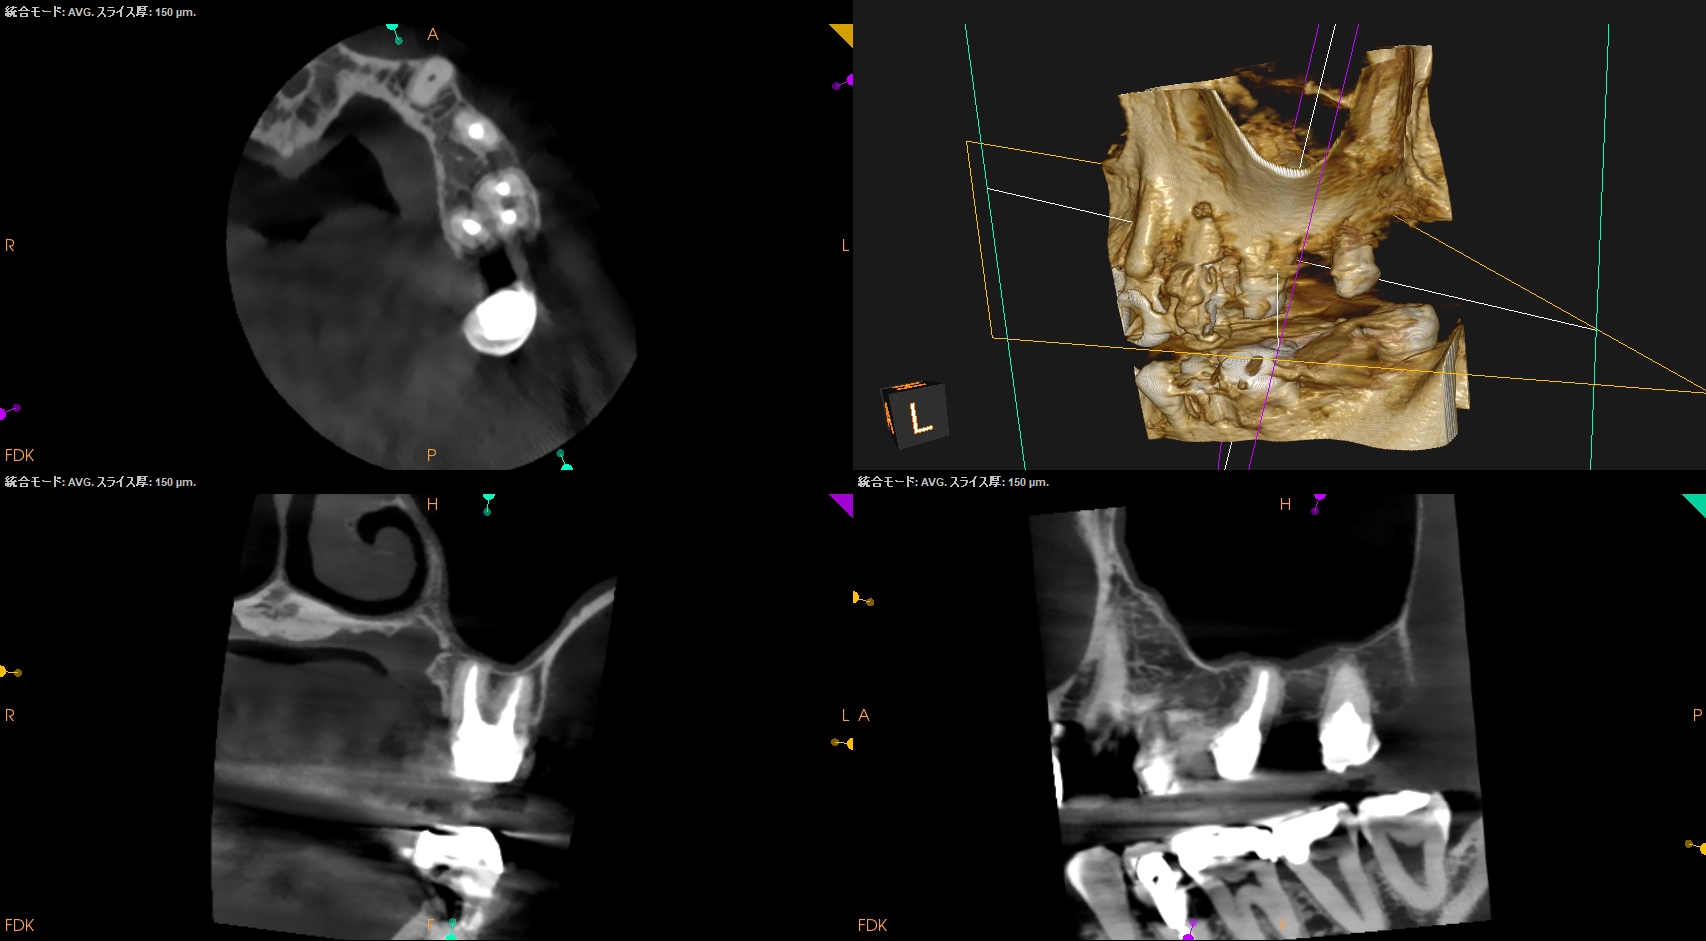

CBCT(2024.7.1)

#3

MB

DB

P

MB,DB,Pと3根全てに病変がある。

しかも形成が不完全だ。

再根管治療が濃厚である。